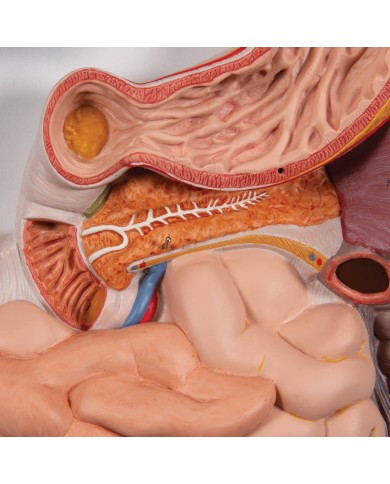

I Modelli anatomici 3B scientific ed Erler Zimmer sono quanto di meglio esista per studiare l'anatomia del corpo umano, il catalogo dei modelli anatomici comprende modelli di cranio, scomponibili, colorati, crani anatomici, crani su cavalletto, e il modello di punta, il cranio in 22 parti, ad incastro magnetico.

Modelli anatomici di articolazioni del piede, ginocchio, gamba, mano, gomito, spalla, bacino, modelli anatomici funzionali di articolazioni anche su cavalletto. Studio dell'articolazione dell'anca. Inoltre ci sono i modelli di scheletro umano completo, da appendere o su cavalletto, con numerazione delle ossa, o flessibili, in modo che i movimenti delle articolazioni dello scheletro umano siano tutte perfettamente riproducibili.

Questo e tanto altro ancora trovi nella sezione dedicata ai modellini anatomici, occhi, denti, orecchio, naso e gola, e i modelli anatomici per ostetricia e ginecologia, per lo studio dell'anatomia della pelvi e del bacino umano.

I modelli anatomici didattici sono riproduzioni di strutture anatomiche perfettamente uguali a quelle vere, i modelli di ossa sono realizzati dalla scansione di ossa vere, l'esperienza tattile è assolutamente realistica, ed anche il peso delle ossa corrisponde all'incirca al peso delle ossa vere.